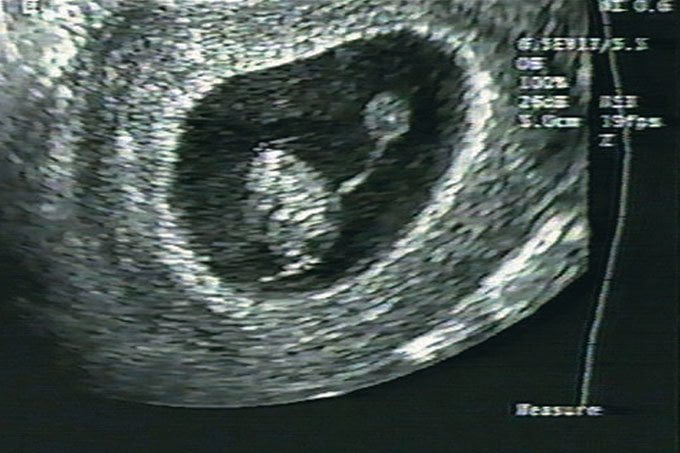

Ultrassom na gravidez: quantos a grávida tem que fazer?

A ultrassonografia será sua grande companheira durante todo o pré-natal. Com ela, você poderá acompanhar o crescimento do bebê e até mesmo ver a…

Ultrassom: o que é, como é feito e para que serve

Também chamado de ultrassonografia e ecografia, o ultrassom é um exame de imagem realizado por um transdutor, aquele aparelhinho que o médico encosta na…